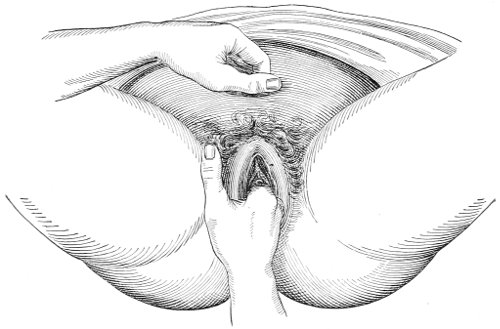

In making the bimanual examination the structures 25 should be palpated methodically in order. The vaginal finger notes the condition of the cervix uteri. If the fundus be in the normal position, the uterus can then be taken between the abdominal hand (upon the fundus) and the vaginal finger (upon the cervix) (Fig. 3). The shape, size, mobility, and consistency are noted. The vaginal finger is then passed anteriorly and laterally toward either uterine cornu, while the abdominal fingers pass over to the posterior aspect of the same cornu. The ovarian ligament and the proximal end of the Fallopian tube may thus be felt. Passing farther outward, the whole of the tube and the ovary may be examined. The same procedure is then applied to the opposite side.

Fig. 3.—Bimanual examination; median sagittal section of the pelvis.

The condition of the ureters may be determined by placing the vaginal finger in either lateral vaginal fornix and drawing it outward and forward, when these structures will pass over the end of the finger. When the 26 ureters are indurated by inflammation they can be plainly felt.